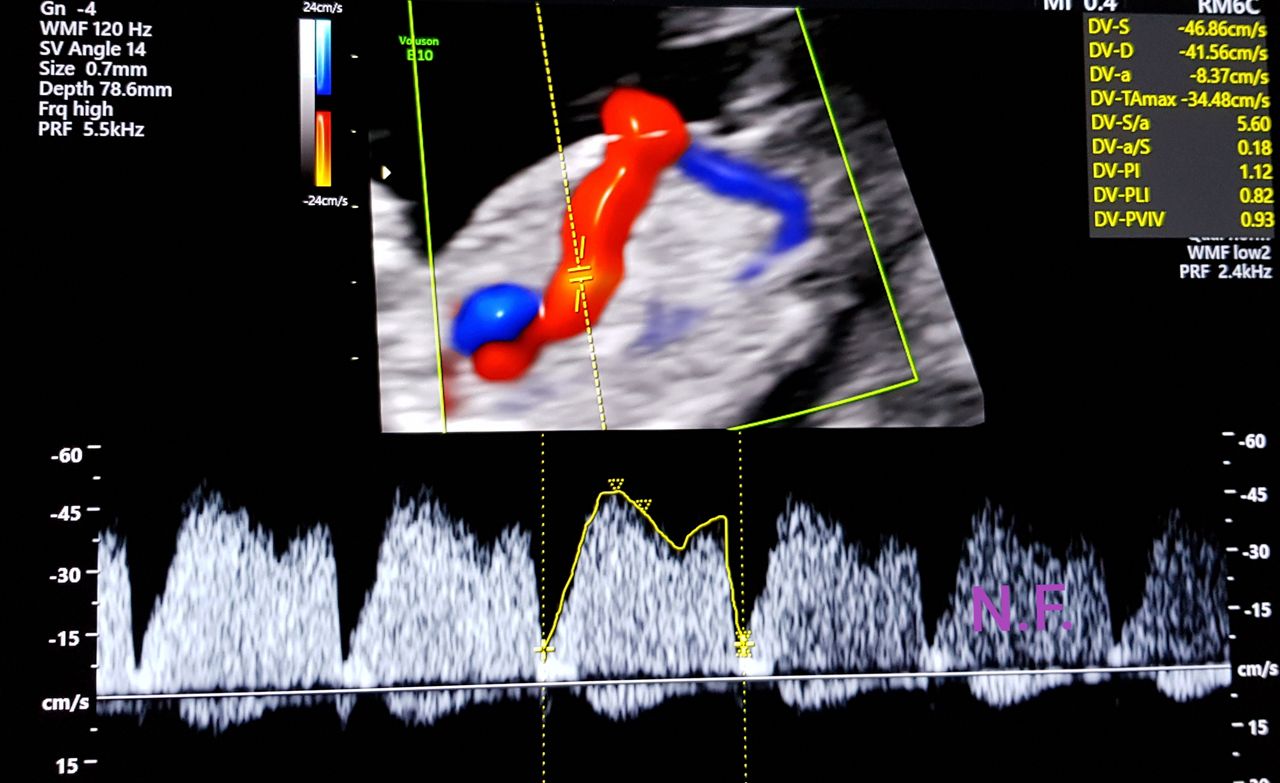

Foto e video